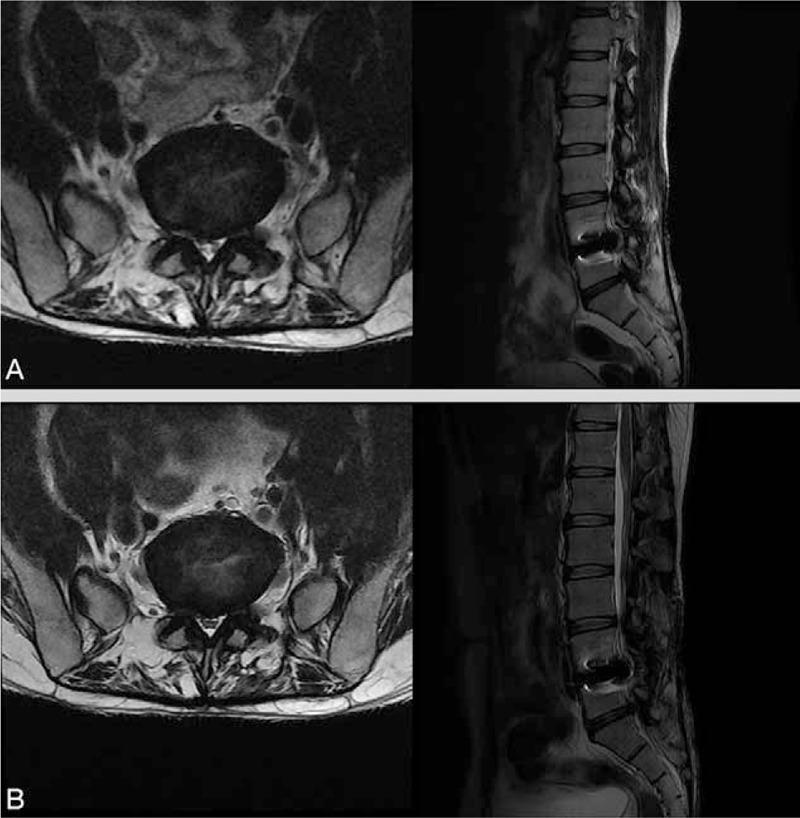

A 36-year-old man received SELD with YAG laser for controlling LBP and radicular pain due to HLD on L5-S1. However, after SELD, voiding and defecation difficulties and sensory deficits on the S3-5 dermatome were presented.

An areflexic neurogenic bladder was demonstrated by a urodynamic study four days after onset of sacral nerve root injury symptoms. In the electromyogram study, latency of electrically induced bulbocavernosus reflex (BCR) was delayed on both sides at four days after symptom onset. Based on the patient's symptoms and the results of the clinical evaluation, we diagnosed the patient as having an injury in the sacral nerve roots.

In this study, we described a patient who showed neurogenic bladder and bowel and sensory deficits in the S3 to S5 dermatome due to sacral nerve root injury after SELD. During SELD, clinicians should be mindful of the possibility of injury to sacral nerve roots.

一名36岁男性因L5-S1节段HLD导致的LBP和放射性疼痛接受了YAG激光SELD治疗。然而,SELD术后出现了排尿和排便困难以及S3-5皮节感觉障碍。

骶神经根损伤症状出现四天后,尿动力学检查显示为无反射性神经源性膀胱。在肌电图检查中,症状出现四天后双侧电诱发球海绵体反射(BCR)潜伏期延迟。根据患者症状和临床评估结果,我们诊断该患者为骶神经根损伤。

在本研究中,我们描述了一名患者,其在SELD后因骶神经根损伤出现神经源性膀胱和肠道功能障碍以及S3至S5皮节感觉障碍。在SELD过程中,临床医生应注意骶神经根损伤的可能性。